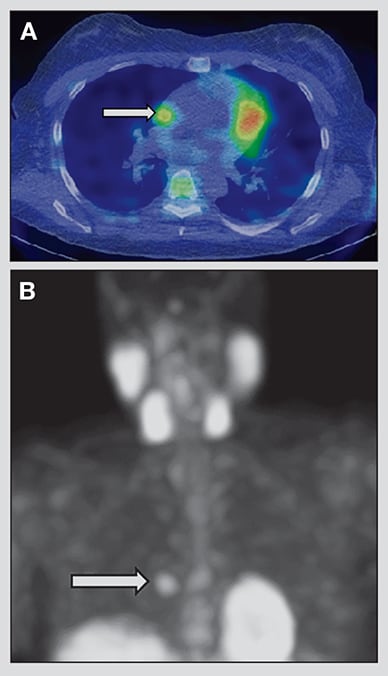

Her laboratory evaluation at Mayo Clinic was consistent with persistent primary hyperparathyroidism. Parathyroid sestamibi imaging with single-photon emission computerized tomography (SPECT) showed ectopic sestamibi uptake in the lower right midchest without discordance in the neck on planar images.

SPECT images confirmed an approximately 1-cm soft tissue nodule in the right paracardiac fat superiorly and just anterior and to the right of the lower superior vena cava and above the right atrial junction, consistent with a solitary parathyroid gland in the anterior mediastinum.

Axial and coronal images from SPECT scan

Axial (A) and coronal (B) images from parathyroid sestamibi SPECT scan demonstrating right paracardiac soft tissue nodule with intense sestamibi uptake (arrows).